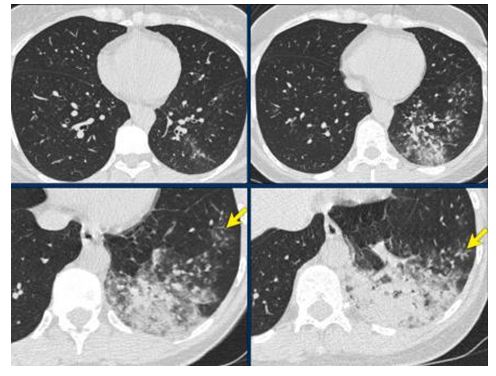

CO-RADS 2: Hình 2 – 3 – 4

Hình 2: Hình ảnh tổn thương CT: “Tree-in-bub sign” vùng ngoại vi phân thùy sau dưới bên phải, giãn & dầy nhẹ thành phế quản vùng trung tâm thùy dưới phổi trái. Không thấy tổn thương GGO. (Tổn thương giống viêm phế quản hơn COVID 19)

Hình 3: Hình ảnh tổn thương CT bao gồm giãn & dầy nhẹ thành phế quản, “tree-in-bub sign” & hình đông đặc. Không thấy tổn thương GGO.

Hình 4: Hình ảnh tổn thương CT bao gồm đông đặc thùy phổi & “tree-in-bub sign” (mũi tên). BN bị viêm phổi do nhiễm khuẩn lan tràn theo đường phế quản (dấu hiệu búp cây).